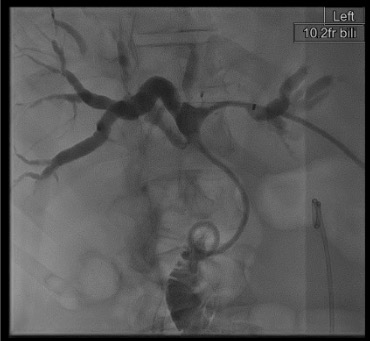

Cholangiogram

Bilateral obstruction — Klatskin tumor

Likely cause: Bismuth III-IV hilar cholangiocarcinoma obstructing both right and left hepatic duct systems independently.

Next step: May need two separate drains (left + right system). Ideally placed same session if patient tolerates; otherwise staged 48 hours apart. Limit to draining the two ducts providing the most functional liver volume. Bismuth IV bilateral drainage rarely achieves meaningful benefit — limit attempts.